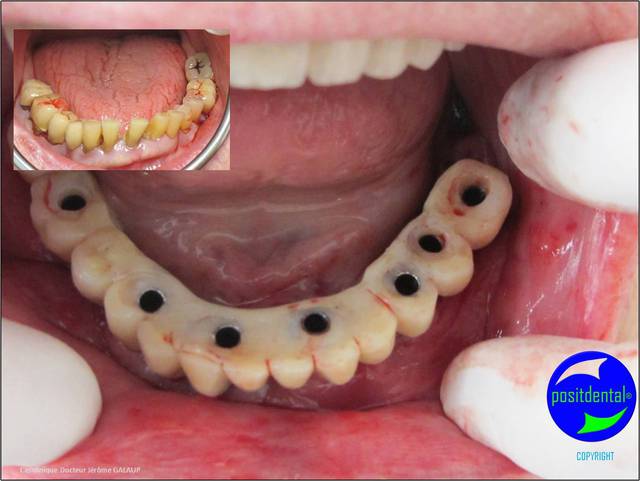

photo pré opératoire

3D maxillaire inférieur et photo